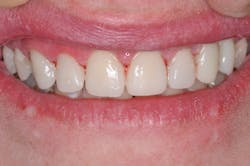

Although four-year cases with Activa have been reported, only time will tell what the longevity of this case will be. So far, the case is at six months and counting confidently (figures 8 and 9). The durability of Activa has been reported in the literature. A patented, rubberized-resin molecule in the resin matrix absorbs shock and stress, and provides unique flexural strength that resists chipping and fracture. A far more expensive option that requires laboratory-fabricated porcelain crowns might provide a more esthetic result, but it was not a viable possibility in this case. The esthetic outcome achieved with this direct restorative technique is very good, and we know we did the right thing for this particular patient.

At the post-operative visit two weeks later, the contacts were perfect, and I achieved anterior disclusion in all excursions. No other refinement of the restorations was needed other than polishing of the surfaces, which required minimal effort. Activa has a chameleon effect that blends shades and reflects adjacent hues to create a natural esthetic.